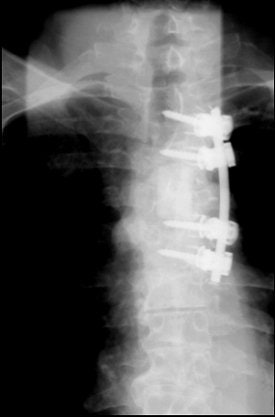

CT also can aid in finessing corpectomy procedures done to treat burst fractures. El-Khoury described an emergency case in which imaging saved the patient from further disaster (images A-F below).

"This patient arrived at the ER paraplegic. We see a little compression here, but we cannot see the entire problem. When we do CT, we see that this is a huge burst fracture. This was fairly acute. (The surgeon) did a corpectomy, which we followed with CT. He put a graft, two levels above and below the fusion," El-Khoury said. "When we looked closely at the CT, we noticed that the lower two screws are sitting and indenting the aorta. We called the surgeon and told him this: 'You have a situation in which you have metal screws pulsating against an aorta, and you know who is going to win in the end.' So the surgeon did an angiogram. The surgeon went in, removed the screws, and fused the patient from the back."